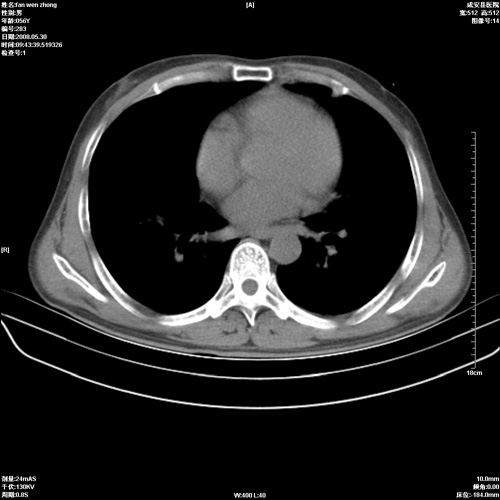

病人 男 56岁 一周前高热,体温达39-40度,经抗炎治疗后,体温渐降,达37,5-38度,轻微咳嗽,胸部不适 查白细胞为1.3万 行ct检查,请分析。

双肺内可见多发结节状病灶,并见小空洞,病人高热,白血球增高,应该是典型的迁徙性肺脓肿(多为金黄色葡萄球菌感染)。查一下口腔等其它部位有无感染灶。

双肺内可见多发结节状病灶,并见小空洞,病人高热,白血球增高,应该是典型的迁徙性肺脓肿(多为金黄色葡萄球菌感染)。建议治疗后复查.